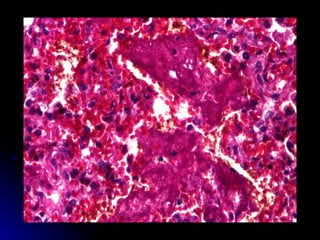

Pulmonary haemorrhage Clinical Sudden deterioration Copious bloody secretions from airway Hypotension Pallor Hypoxaemia

Pulmonary haemorrhage -Aetiology Usually preterm HMD with PDA Post surfactant therapy Coagulopathy Congestive cardiac failure

Pulmonary haemorrhage - Treatment Ventilation with high PEEP Surfactant Indomethacin for PDA Treat coagulopathy

Pulmonary haemorrhage ClinicalSudden deterioration Copious bloody secretions from airway Hypotension Pallor Hypoxaemia

Pulmonary haemorrhage -AetiologyUsually preterm HMD with PDA Post surfactant therapy Coagulopathy Congestive cardiac failure

Pulmonary haemorrhage -Treatment Ventilation with high PEEP Surfactant Indomethacin for PDA Treat coagulopathy